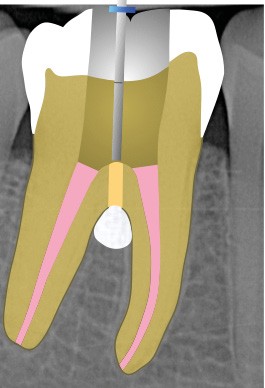

Perforation infra-osseuse avec accès visuel direct (fig. 3)

Ce type de perforation est également la plupart du temps iatrogénique et survient lors de la recherche ou de la mise en forme canalaire, lors de la préparation pour un logement de tenon radiculaire. Situées au niveau du plancher pulpaire des dents pluriradiculées, ou au niveau des entrées canalaires des dents monoradiculées ou pluriradiculées, il s’agit le plus souvent de perforations à quatre parois. Si la perforation survient en cours de traitement, elle doit être gérée immédiatement pour un meilleur pronostic (fig. 4). Néanmoins, il est important de prendre en compte l’épaisseur résiduelle du plancher. Si le plancher est trop fin, il ne sera pas possible d’envisager de traiter la perforation.